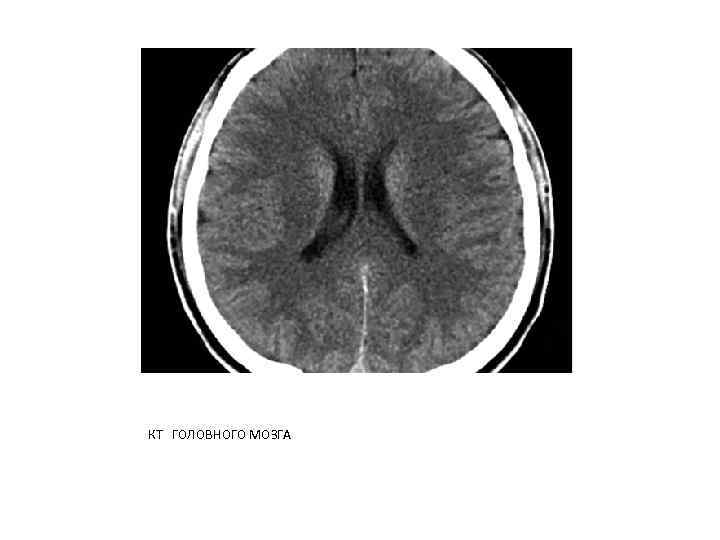

РЕНТГЕНОВСКАЯ КОМПЬЮТЕРНАЯ ТОМОГРАФИЯ КТ является наиболее информативным методом лучевой диагностики повреждений черепа и головного мозга. При клинических показаниях и доступности КТ следует выполнять до проведения любых рентгеноконтрастных исследований.

Возможности выявления различных заболеваний и повреждений головного мозга с помощью КТ связаны либо с нарушением нормальных анатомических взаимоотношений в полости черепа, либо с различным ослаблением рентгеновских лучей нормальными и патологически измененными тканями.

В норме на компьютерных томограммах может наблюдаться физиологическая кальцификация вещества и оболочек головного мозга. Участки обызвествления могут располагаться в шишковидной железе, сосудистых сплетениях боковых желудочков. Определены денситометрические показатели структур головного мозга в относительных единицах (шкала Хаунсфилда - HU). Так, плотность серого вещества составляет +30. . . +35 HU, белого +25. . . +29 HU

КТ ГОЛОВНОГО МОЗГА